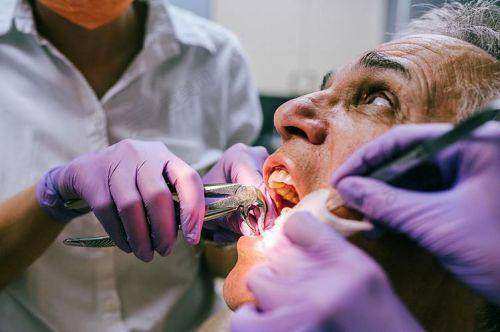

烟台莱山德韩口腔门诊部成立于2022年6月20日,公司规模为100 - 499人。门诊部设有多个专精科室,涵盖了口腔种植、口腔正畸、口腔修复、口腔综合治疗等多个领域。其中,数字化种植中 心和美颜正畸中 心是其特色科室。数字化种植中 心配备了德国卡瓦口腔CT、3D导板打印系统等精良设备,实现了“数字化种植”,能够为患者提供精细、效率高的种植方案。美颜正畸中 心引入了美国隐适美iTero口扫仪,5分钟即可生成牙齿3D模型,并动态演示矫正全过程,为患者提供个性化的正畸方案。此外,门诊部还注重服务质量和患者体验,为患者提供全方面的口腔医疗服务。

烟台莱山德韩口腔门诊部拥有多个特色项目,具有显著的独特之处和优势。在数字化种植中 心,配备德国卡瓦口腔CT、3D导板打印系统,实现“数字化种植”。ALL - ON - 4半口种植仅需4颗植体半口牙,支持即刻负重,术后24小时戴临时冠;百康特种植套餐1280元起(含植体 + 基台 + 牙冠),瑞士诺贝尔高端植体可选,能有效避开神经,全程几乎微痛。美颜正畸中 心引入美国隐适美iTero口扫仪,5分钟生成牙齿3D模型,并动态演示矫正全过程。金属自锁托槽矫正周期缩短30%,儿童配合度更高;隐形矫正双膜技术(时代天使/隐适美),薄厚膜交替佩戴加速牙齿移动;价格透明,金属托槽4980元起,全隐形矫正8888元起(2025年活动价)。此外,门诊部还设有独立诊室,搭配空气系统,保护隐私的同时降低交叉感染风险;器械消毒采用“六步灭菌法”,实现“一人一机一用”。

虽然目前没有详细的医生个人信息,但烟台莱山德韩口腔门诊部汇聚了一批专精的口腔医生团队。他们均具备丰富的从业经验和扎实的专精知识,在各自擅长的领域有着出色的表现。在种植牙方面,医生们能够根据患者的具体情况,制定个性化的种植方案,确保种植成效和安心性;在正畸领域,医生们熟练掌握各种正畸技术,能够为患者提供美观、舒适的正畸治疗。此外,医生们还注重与患者的沟通和交流,耐心解答患者的疑问,让患者在就诊过程中感受到专精和温暖。